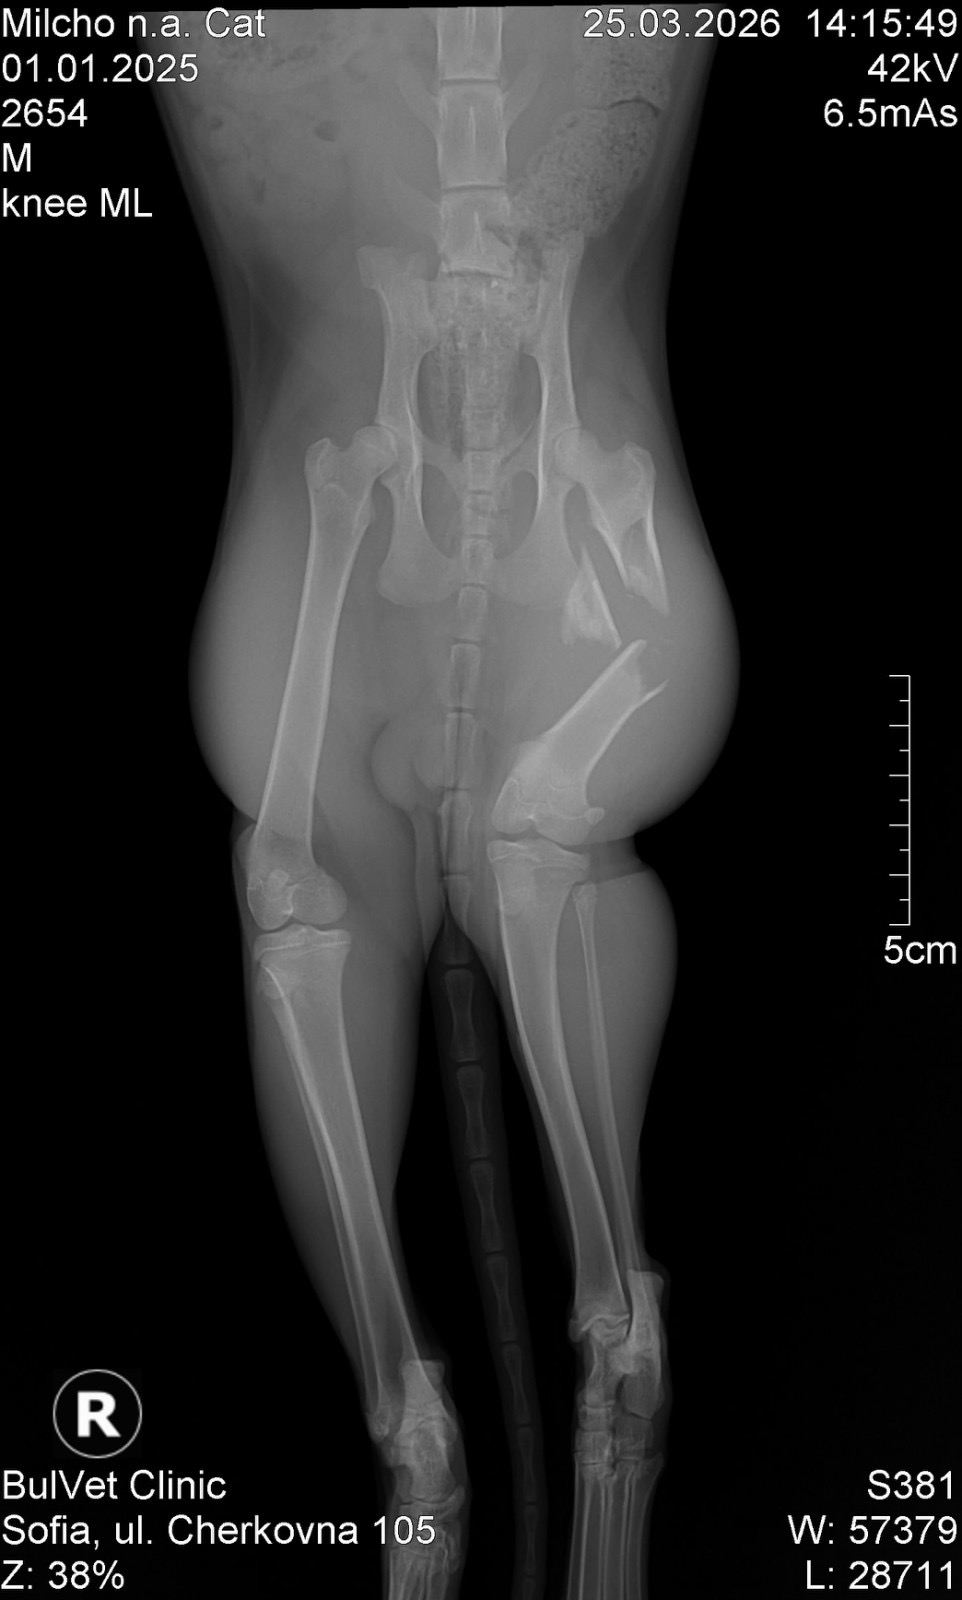

Искаме да ви запознаем с едно малко геройче – котето Милчо, което цяла седмица се въртеше из групите с надеждата някой да му помогне…Милчо е от Петрич, но там не се намери възможност да бъде опериран. Успяхме да го транспортираме до София, където днес му беше направен специализиран ортопедичен преглед… и новините не са добри.

Милчо е със:

– сериозна фрактура на крачето( снимки от рентген - в коментарите)

– множество счупвания

– травми в областта на таза

– силно изтощен и дехидратиран

Очевидно са минали дни след удара, който е преживял…

Съединителната тъкан вече започва да се разраства, което означава само едно — НЯМАМЕ ВРЕМЕ.Операцията трябва да се направи СПЕШНО, ако искаме Милчо да има шанс да ходи отново на четири лапички…